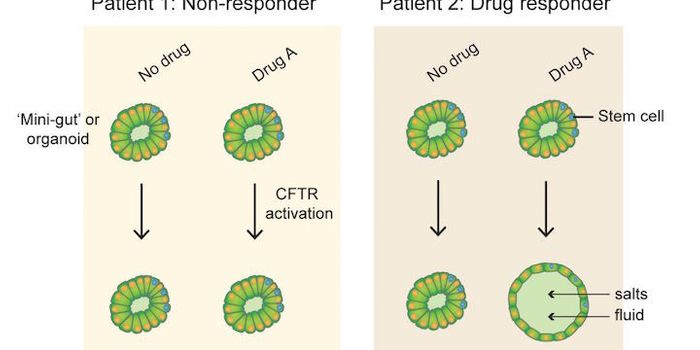

JUN 29, 2016Cell & Molecular BiologyOrganoids, basically a small in vitro model of an organ, could aid in identifying the best therapies for some people suf ...